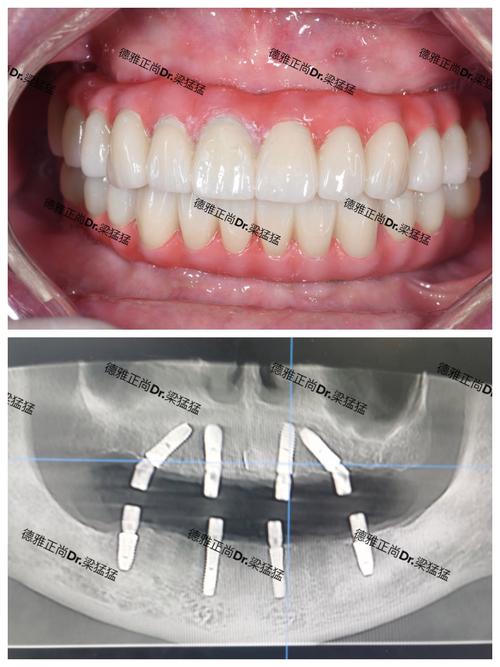

- 数字化导板: 对于复杂病例或要求高精度的病例,可能利用术前CBCT数据制作数字化手术导板,引导种植体植入,提高精度和安全性。

- 牙冠制作与安装:

- 愈合基台安装后,牙龈形态稳定(通常需要1-2周)。

- 使用数字化口内扫描仪或传统取模方式获取印模。

- 技工室根据印模和医生要求制作牙冠(基台+牙冠)。

- 试戴牙冠,检查形态、颜色、咬合关系是否合适。

- 确认无误后,永久粘固或螺丝固位在种植体上。